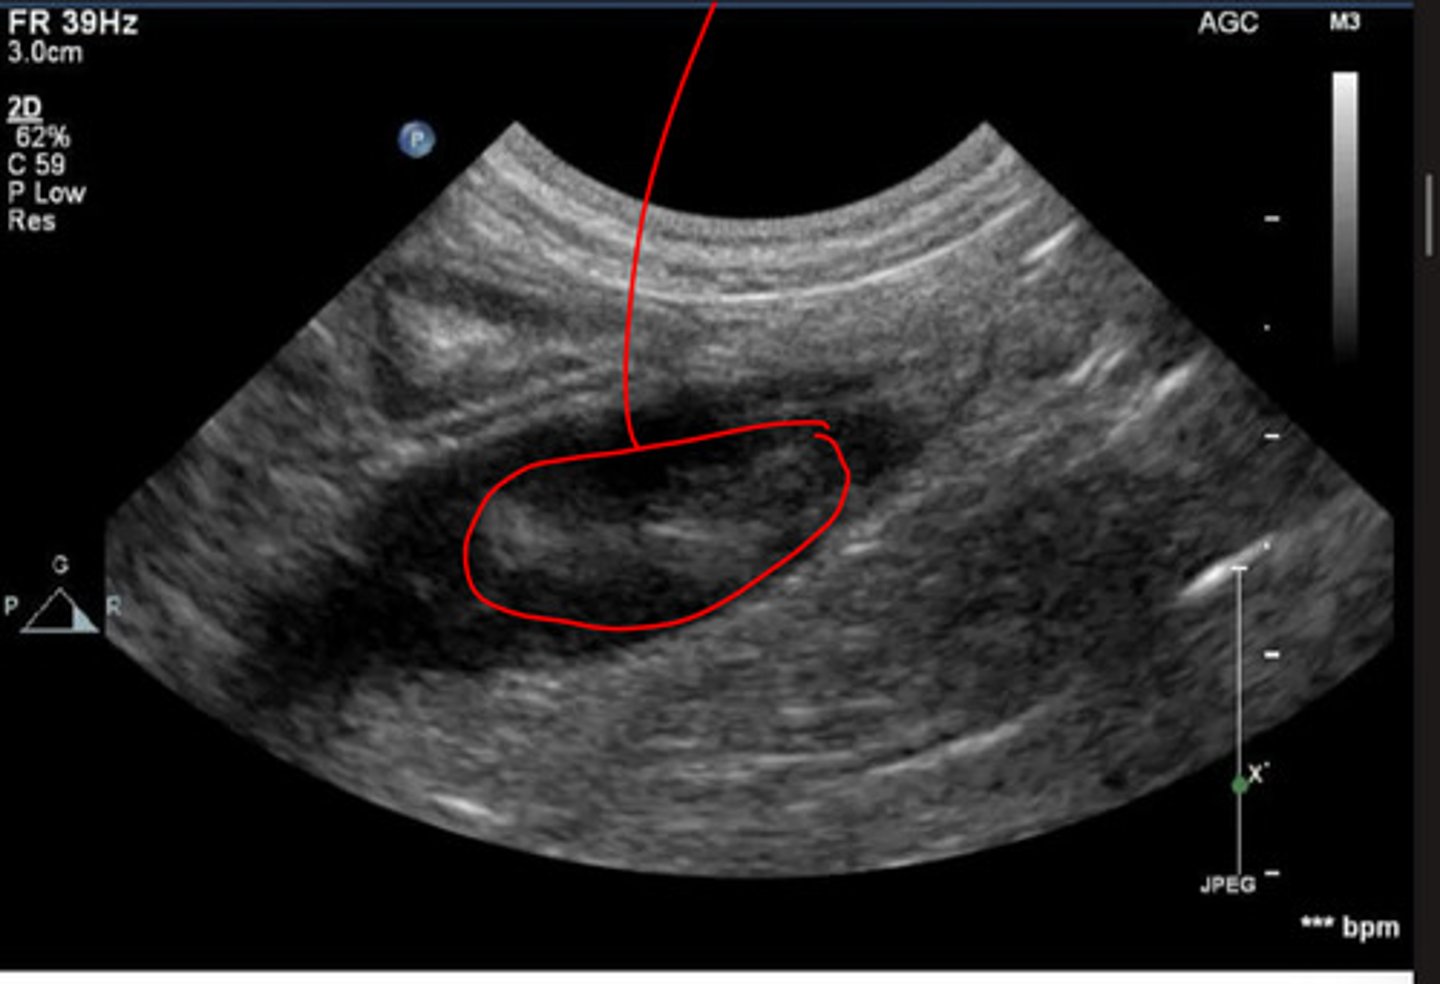

dilation of abdominal aorta

what is the abnormality in this aorta indicated by the red?